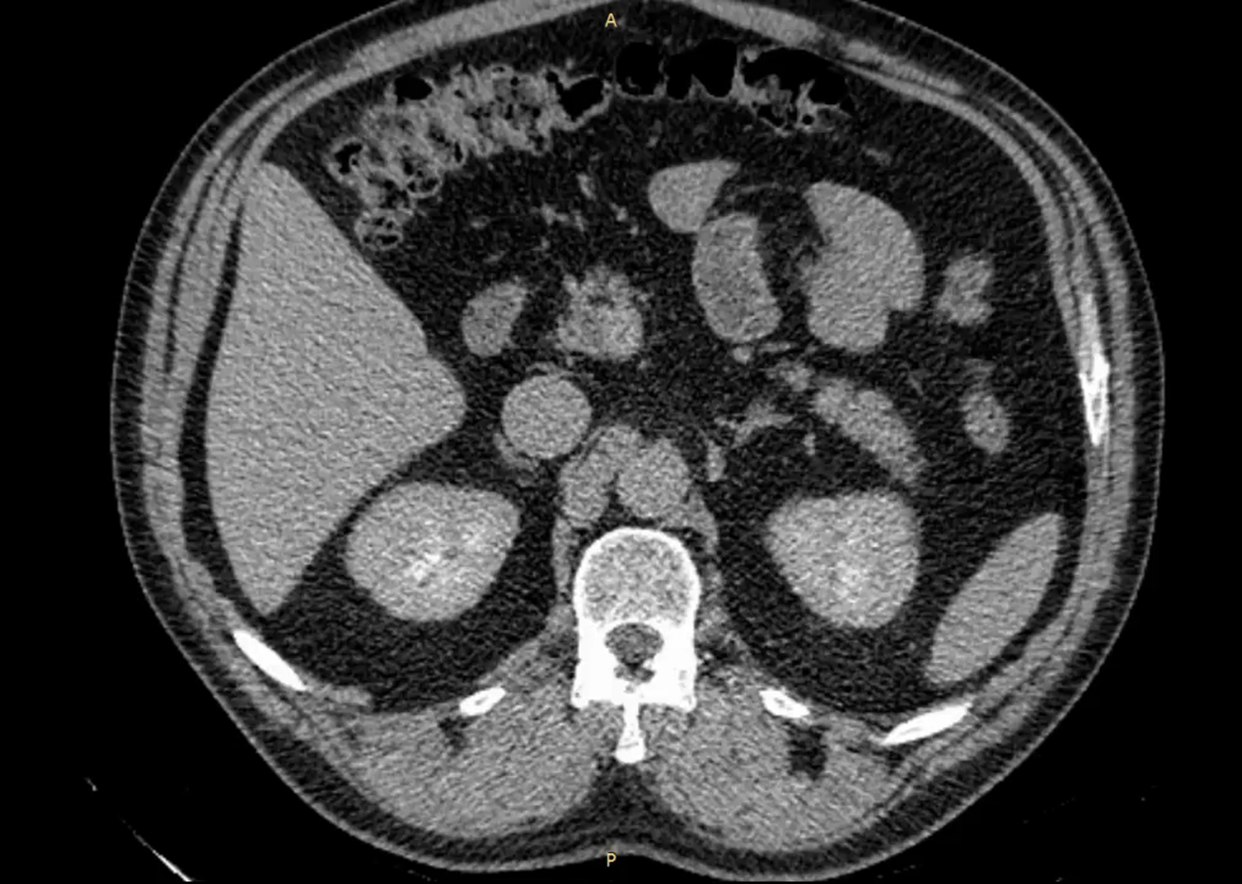

Мужчина 52 лет наблюдался в поликлинике с доброкачественным новообразованием в почке. Его беспокоили периодические боли в пояснице слева. Ранее выявленная киста почки росла, вызывая нарушение оттока мочи и угрозу снижения функции почки.

Хирургическое удаление кисты в данном случае было невозможно из-за расположения кисты внутри почки. Вмешательство могло привести к потере органа.

Врач-уролог, заведующий отделением урологии №2 клиники "Нефтяник" Владимир Новоселов: "Суть метода заключается в создании сообщения между полостью кисты и чашечно-лоханочной системой почки. Мы изучали КТ-снимки, архитектонику почки, чтобы свести к минимуму определенные риски травмирования сосудов почки. Операция прошла в штатном режиме".